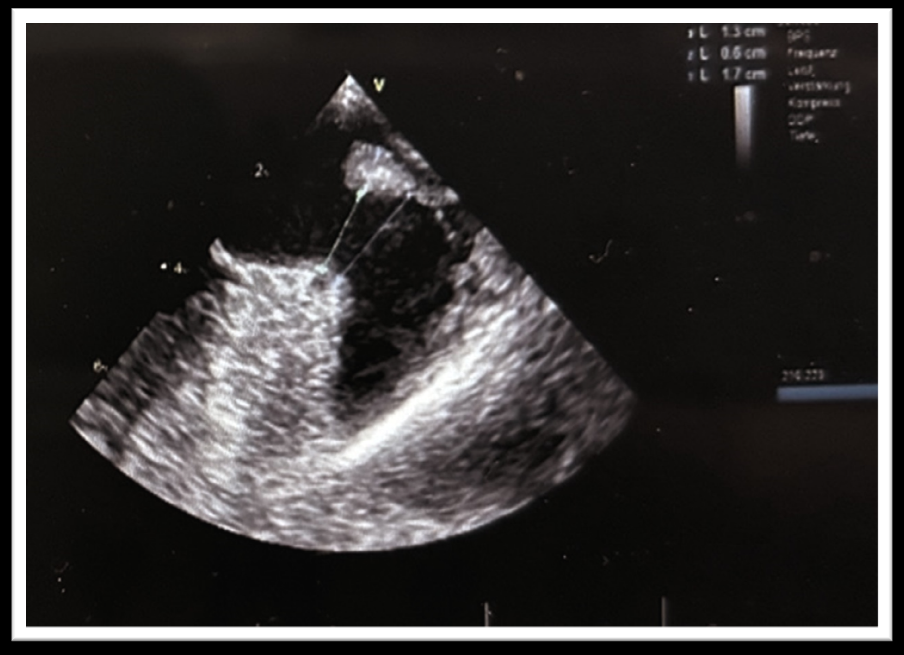

在LSPV中,将 Faradrive® 鞘管通过导丝置换成 Boston Scientific双向可调弯 14Fr 输送鞘管。使用 6 Fr猪尾巴导管将WATCHMAN14Fr 输送鞘管引导至 LAA,并在RAO30°、CRA15° 和CAU20° 角度下进行造影。造影或 TEE 上的 LAA 着陆区最大直径为 22.8 mm(图1),因此选择了WATCHMAN FLX™ 27 mm封堵器。该封堵器在LAA中推送(图 2),并且可以在第一次尝试时成功植入,而无需重新定位。在多普勒序列中,没有观察到残留漏。患者出院时接受了双重治疗,即每日两次服用150mg达比加群作为直接口服抗凝剂 (DOAC) + 阿司匹林,并计划在手术后 6 周进行TEE随访。有趣的是,TEE 显示嵴部部水肿完全消退,封堵器近端轻微移动。压缩保持22mm,封堵令人满意,因此DOAC治疗(每日两次服用150mg达比加群)中断,继续服用阿司匹林。在 6个月的随访期间,未记录到中风或出血,也未记录到复发的房颤。

图表1 经食道超声心动图测量左心耳着陆区的最大直径为 22.8mm

已经报道过同时进行左心耳封堵术和 PVI射频消融。在刚消融的组织上植入封堵器可能会因封堵器残余漏而导致封堵器脱落的风险。但是,Surpass Registry报告称,在45天的随访中,联合使用 PVI +左心耳封堵术与单独使用左心耳封堵术之间封堵器周围残余漏的程度没有差异。由于PFA具有不同的病变损伤机制,我们预计在 LAA 底部观察到的可能影响LAA封堵的水肿较少。如图3所示,事实并非如此:观察到 LAA-PV 嵴部(与组织直接接触的部位:Basket/Olive结构)明显水肿(0.8 厘米),与 6 周随访 TEE 图像相比尤其明显,6周水肿完全消退(0.4 厘米)。水肿被认为在口部而不是着陆区内,因此左心耳封堵术顺利完成。然而,仔细比较 TEE 后续图像后发现,封堵器近端微小倾斜,但并不影响LAA的密封性和封堵器的稳定性。

图表3手术期间观察到的 LAA-PV嵴部的经食道超声图像明显水肿(0.8 厘米),与 6 周随访经食道超声图像相比,水肿完全消退,水肿大小为 0.4 厘米